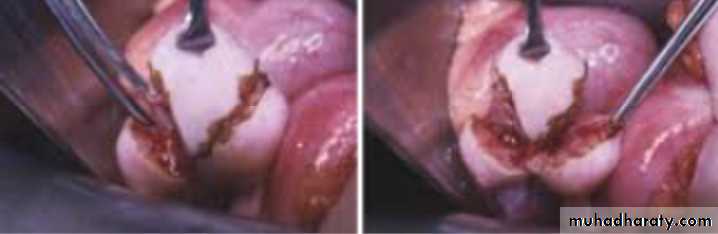

What is this procedure : wedge resection part of surgical tx in case of PCOS